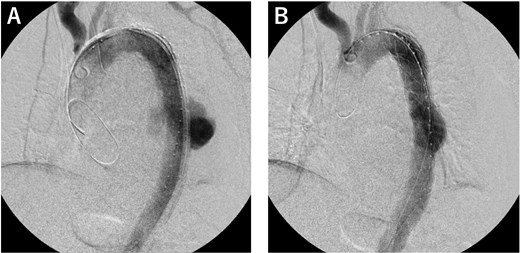

An 81-year-old male patient was transferred to our institution with chest radiographic abnormalities and an increased inflammatory response. The patient had a fever 2 weeks before admission, was diagnosed with a urinary tract infection (UTI), and was treated with oral levofloxacin (LVFX) by the patient’s doctor. The fever reduced following the administration of LVFX; however, follow-up chest radiography revealed an abnormal shadow in the left lung field (Fig. 1A). On admission, the physical examination results were normal: afebrile, no haemodynamic instability, and no specific symptoms. Contrast-enhanced computed tomography (CECT) revealed a thoracic aortic rupture (Fig. 1B and C). Therefore, the patient underwent emergency thoracic endovascular aortic repair (TEVAR) with a Zenith Alpha (32 × 155 mm; W. L. Gore & Associates, Flagstaff, AZ). The operation was successfully performed with no obvious complications (Fig. 2).

Operative findings. (A) We deployed a Zenith Alpha (32 × 155 mm; W. L. Gore & Associates, Flagstaff, AZ) in the descending aorta, covering the rupture site. (B) The final study confirmed loss of the contrast effect in the aneurysm and no obvious endoleak.